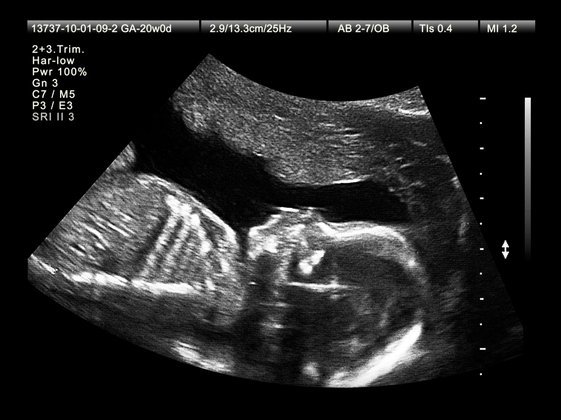

Vielleicht merkt ihr in SSW 19 die Purzelbäume, die das Baby schlägt? Das Kind ist jetzt schwerer und größer als die Plazenta. | 24 cm | 200 g | |

Die Gehirnzellen reifen heran und der ganze Körper ist von einem Flaum bedeckt. In der 20. SSW entsteht Babys einmaliger Fingerabdruck. | 25 cm | 300 g | |

Das geschluckte Fruchtwasser wird um die 21. SSW über die Blase wieder ausgeschieden. | 26 cm | 335 g | |

Das Baby übt zu tasten und nimmt in SSW 22 Druck, Schmerz und Licht wahr. | 27 cm | 400 g | |

Ein erster Schlaf- und Wachrhythmus entsteht nun in der 23. SSW. | 28,8 cm | 490 g | |

Babys Geschmackssinn ist in SSW 24 entwickelt. Es greift und lutscht am Daumen. | 31 cm | 550 g | |

Mit dem Fruchtwasser übt das Baby um die 25. SSW zu schlucken. Weiße Blutkörperchen bilden sich. | 34 cm | 650 g | |

Das Baby und seine Knochen werden in SSW 26 immer kräftiger. Vielleicht kann Papa es nun auch spüren? | 35 cm | 750 g | |

Das Baby öffnet die Augen und erkennt in SSW 27 schon Formen, Farben und Umrisse. | 36,3 cm | 900 g | |

Der Schlaf- und Wachrhythmus festigt sich in der 28. SSW und ähnelt oft dem nach der Geburt. | 37,5 cm | 1.000 g |